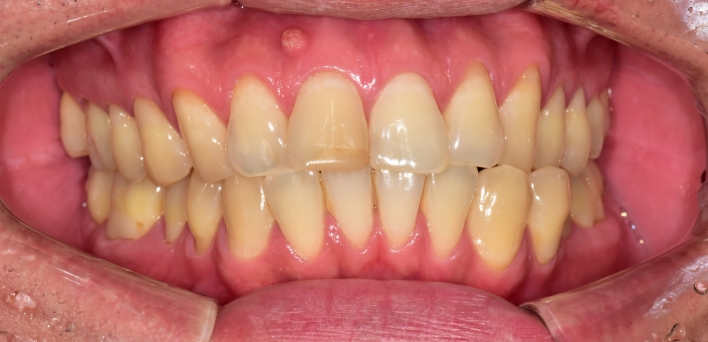

단순하게 예쁘고, 심미적으로 만드는 인위적인 작업물이 아닌,

자연치아와 가장 유사하도록 치아를 복구하는데에 초점을 맞추어

치아복구 + 치아성형 2가지의 장점을 합쳐

개개인 손상 정도에 따른 맞춤형 보철을 제작합니다.

그저 예쁘기만한 부자연스러운 라미네이트가 아닙니다.

더서울치과의원은 각 개인의 얼굴 특성에 맞는 맞춤형 라미네이트를 선물합니다.